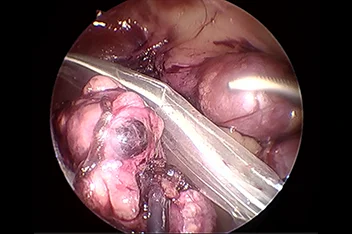

1. 복강경 수술

간단한 중성화부터 부신절제, 간엽절제, 담낭절제 등 고난도 수술까지 적용 가능하며, 대형견에서 특히 효과적입니다.

기존의 개복수술은 충분한 노출을 위하여 복부의 피부와 복벽 근육을 길게 절개해야 합니다.

하지만 복강경을 이용하면 보통 3mm-10mm 직경의 포트를 통해 복강 내에 이산화탄소를 주입하여 공간을 만들고,

카메라를 통해 더 뚜렷하게 시각화할 수 있고 지혈 기구를 통해 장기들을 안전하게 분리하여 절제할 수 있습니다.

복강경의 경우 대형견에서 그 장점이 뚜렷하며 현재는 소형견, 고양이에서도 이러한 장점 때문에 최소 침습 수술을 진행하게 됩니다.

본원에서는 간단한 중성화나 조직생검 외에도 부신절제술, 담낭절제술, 신장절제술, 비장절제술, 간엽절제술 등을 포함한

고난도 수술도 실시합니다.

복강경

담낭절제술, 간생검, 간엽절제술, 신장절제술, 부신절제술, 중성화수술, 잔존난소제거술

• 복강경 비장절제

• 복강경 신장절제